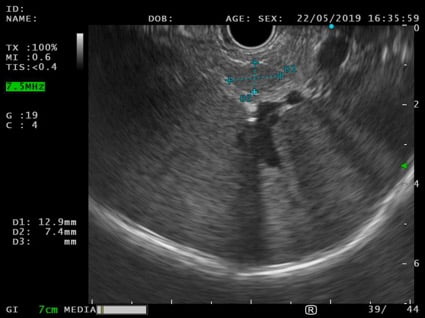

An EUS was therefore performed and a 12x7mm hypoechoic lesion was identified in the pancreatic tail. It was a round-shaped, well-defined, homogeneous intrapancreatic mass (Fig. 3). The lesion characterization was complemented by EUS-elastography, which displayed a homogeneous green elastographic pattern (Fig. 4). The remaining pancreas was unremarkable. EUS-FNB (Acquire – Boston Scientific; 25G, 1 pass) was performed.

Figure 3. EUS (transgastric view): 12x7mm round-shaped, well-defined, hypoechoic, homogeneous lesion in the pancreatic tail.